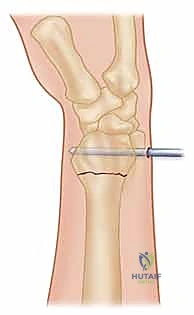

4. إدخال الأسلاك المعدنية (Pinning)

باستخدام مثقاب جراحي كهربائي دقيق، يقوم الدكتور هطيف بإدخال السلك المعدني الأول عبر الجلد، مروراً بالعظم السليم، ثم يعبر خط الكسر ليصل إلى الشظية المكسورة ويثبتها.

هناك عدة تقنيات هندسية لإدخال الأسلاك، أشهرها:

* التثبيت المتقاطع (Cross-Pinning): إدخال سلكين من زوايا مختلفة ليتقاطعا داخل العظم، مما يوفر ثباتاً دورانياً ممتازاً.

* تقنية كابانجي (Kapandji Technique): إدخال الأسلاك مباشرة في خط الكسر واستخدامها كرافعات لرفع العظم المنخسف ثم دفعها في العظم المقابل لتثبيته. يتميز الدكتور هطيف ببراعة فائقة في تطبيق هذه التقنية المعقدة.